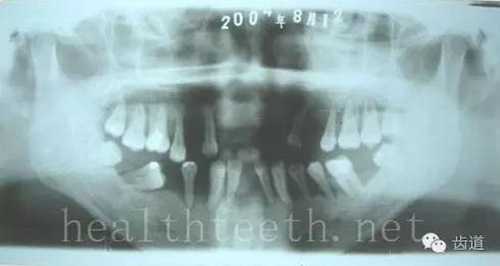

3、多生牙

病例1

47.jpg

48.jpg

49.jpg